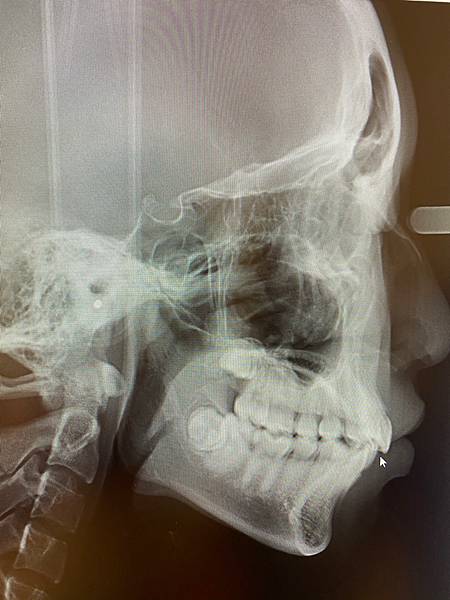

【中壢牙醫推薦】爵士牙醫 隱適美講師蔡孟桓醫師 牙套日記

【中壢牙醫推薦】打骨釘真的很可怕?! 爵士牙醫 蔡孟桓醫師 牙套日記2